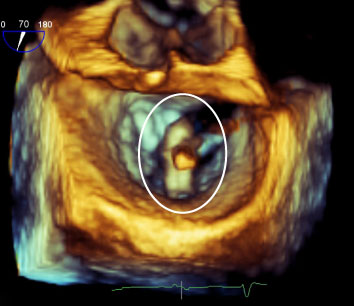

3. Detailed heart ultrasound: You will also need recent transesophageal echocardiogram (TEE) images and reports for a closer look at your valve. A TEE uses ultrasound to create images of your heart with a specialized probe, which is inserted into the esophagus. This test provides information about how large the heart is, how well it contracts, and how the valves function.